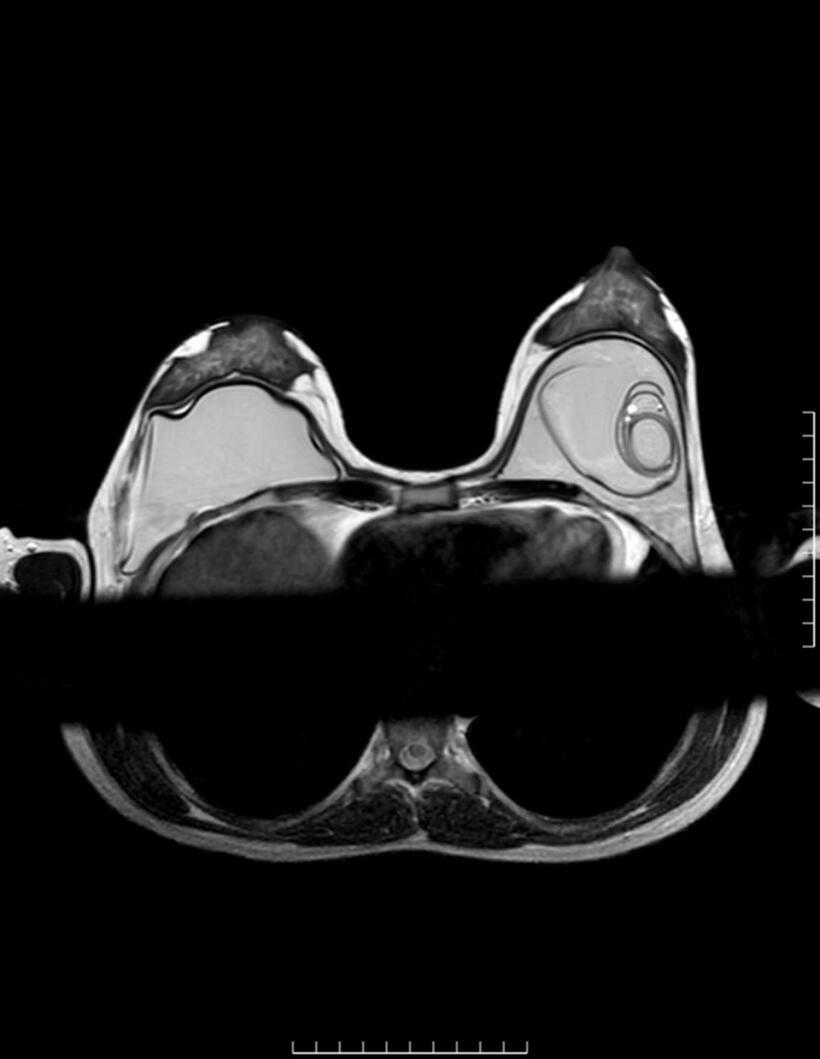

Hình ảnh CT vỡ túi ngực.Ảnh: BSCC

Vỡ túi ngực là tình trạng lớp vỏ implant bị rách hoặc nứt, làm chất bên trong thoát ra ngoài. Với túi nước muối, biểu hiện thường rõ rệt khi ngực xẹp nhanh. Trong khi đó, với túi silicone gel – đặc biệt là loại gel kết dính – silicone có thể vẫn nằm trong bao xơ, khiến hình dạng ngực không thay đổi đáng kể. Đây là lý do nhiều trường hợp được gọi là “vỡ túi thầm lặng”.

ThS.BS Nguyễn Minh Nghĩa khuyến cáo, người đã nâng ngực cần duy trì thăm khám định kỳ để phát hiện sớm các bất thường. Việc theo dõi nên kết hợp khám lâm sàng và các phương pháp chẩn đoán hình ảnh như siêu âm hoặc cộng hưởng từ (MRI).

Thông thường, bệnh nhân nên kiểm tra sau khoảng 5–6 năm kể từ khi đặt túi và tiếp tục theo dõi định kỳ mỗi 2–3 năm. Điều này đặc biệt quan trọng với các trường hợp không có triệu chứng rõ ràng.